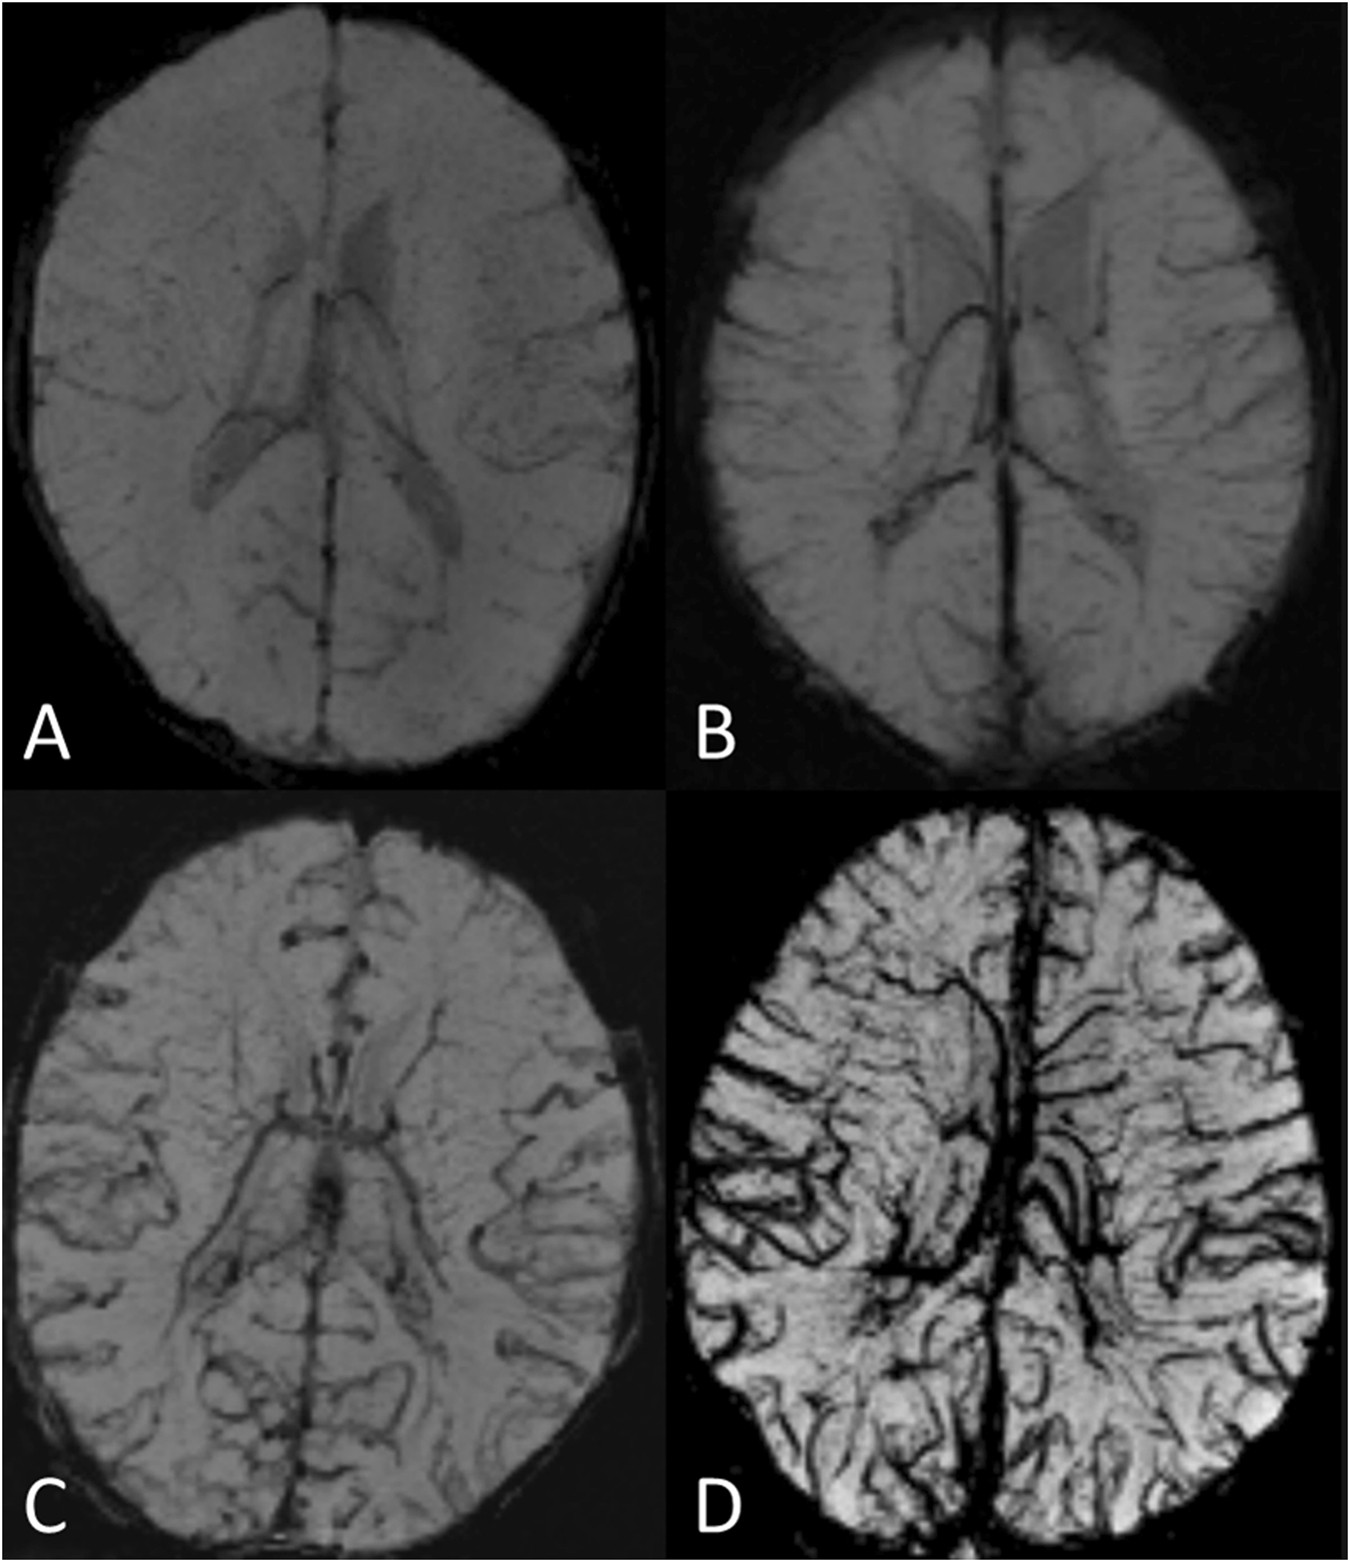

Figure 1

SWI images in minimum intensity projection (miP) as examples of grading of cerebral veins. (A) Grade O: normal appearance of cerebral veins (images of a 2-day-old healthy subject with normal art. oxygen saturation of 95%); (B) Grade 1: mildly prominent deeper veins and cortical veins (patient No. 5). (C) Grade 2: moderately prominent cortical and deeper veins (patient No. 8). (D) Grade 3: distinctly prominent cortical and deeper veins, prominent veins in the semioval centre bilateral (patient No. 1).